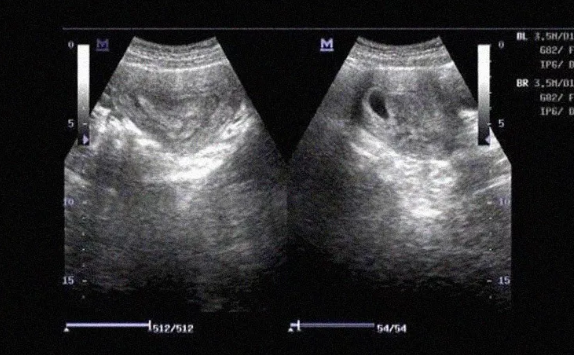

1、完全子宮縱隔:縱隔由宮底到宮頸內(nèi)口或外口; 有些完全子宮縱隔合并陰道縱隔,少數(shù)一側(cè)陰道閉鎖,伴泌尿系統(tǒng)發(fā)育不全。

2、不全子宮縱隔:縱隔終止于宮頸內(nèi)口以上的任何部位,縱隔在外口以上的部位可有交通。